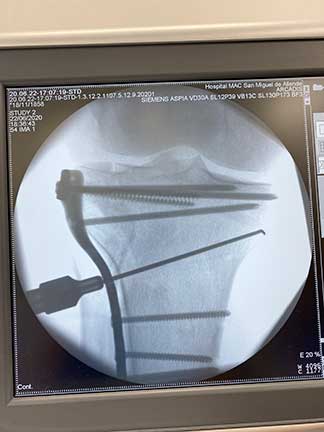

Imagen transoperatoria en fluroscopio de una reducción cerrada de fractura de meseta tibial derecha

El procedimiento es variable, puede ser quirúrgico o conservador dependiendo las características de la fractura y del paciente, el tratamiento que se debe realizar deberá ser planeado y personalizado a cada paciente englobado en colocación de fibras de vidrio, placas, tornillos, clavos o cerclajes.

El objetivo siempre será una reconstrucción anatómica, es decir, una reconstrucción lo más parecida a la anatómica normal previa a la fractura. Para lograr este objetivo es importante que el tratamiento sea realizado por médicos u ortopedistas expertos en fracturas articulares, lo cual mejoraría el resultado.